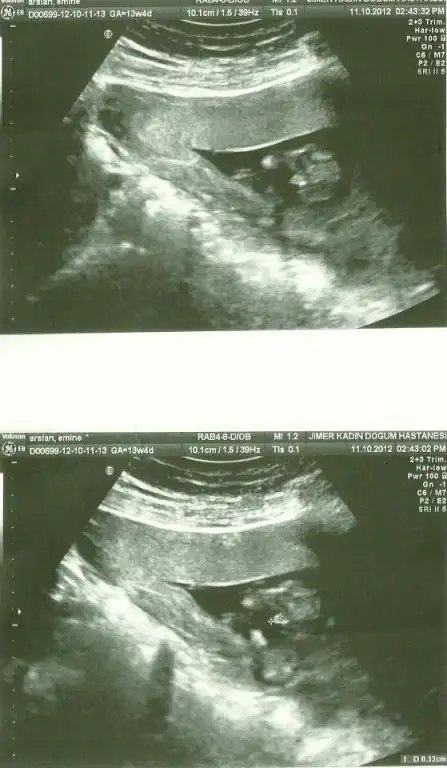

canım inanmayacaksınınz ama cinsiyet aslında altıncı haftasında belli olmaya başlıyorrr bu kadar endişe neden benim arkadaşım 11 haftasında öğrenmiştii ilerleyen zamanlardaa tekrar tekrar sorarsın caınm yaaa dert etmeeee bu arada benimde oğlum olacak inşallah sağlıklı bir şekildee elleri ayakları düzgün sağlıkları yerinde olsunda gerisinin önemi yok canım yaa